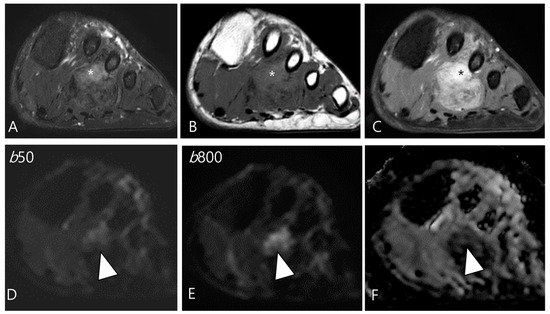

2.5. Advanced MRI Sequences for D-TSGCT